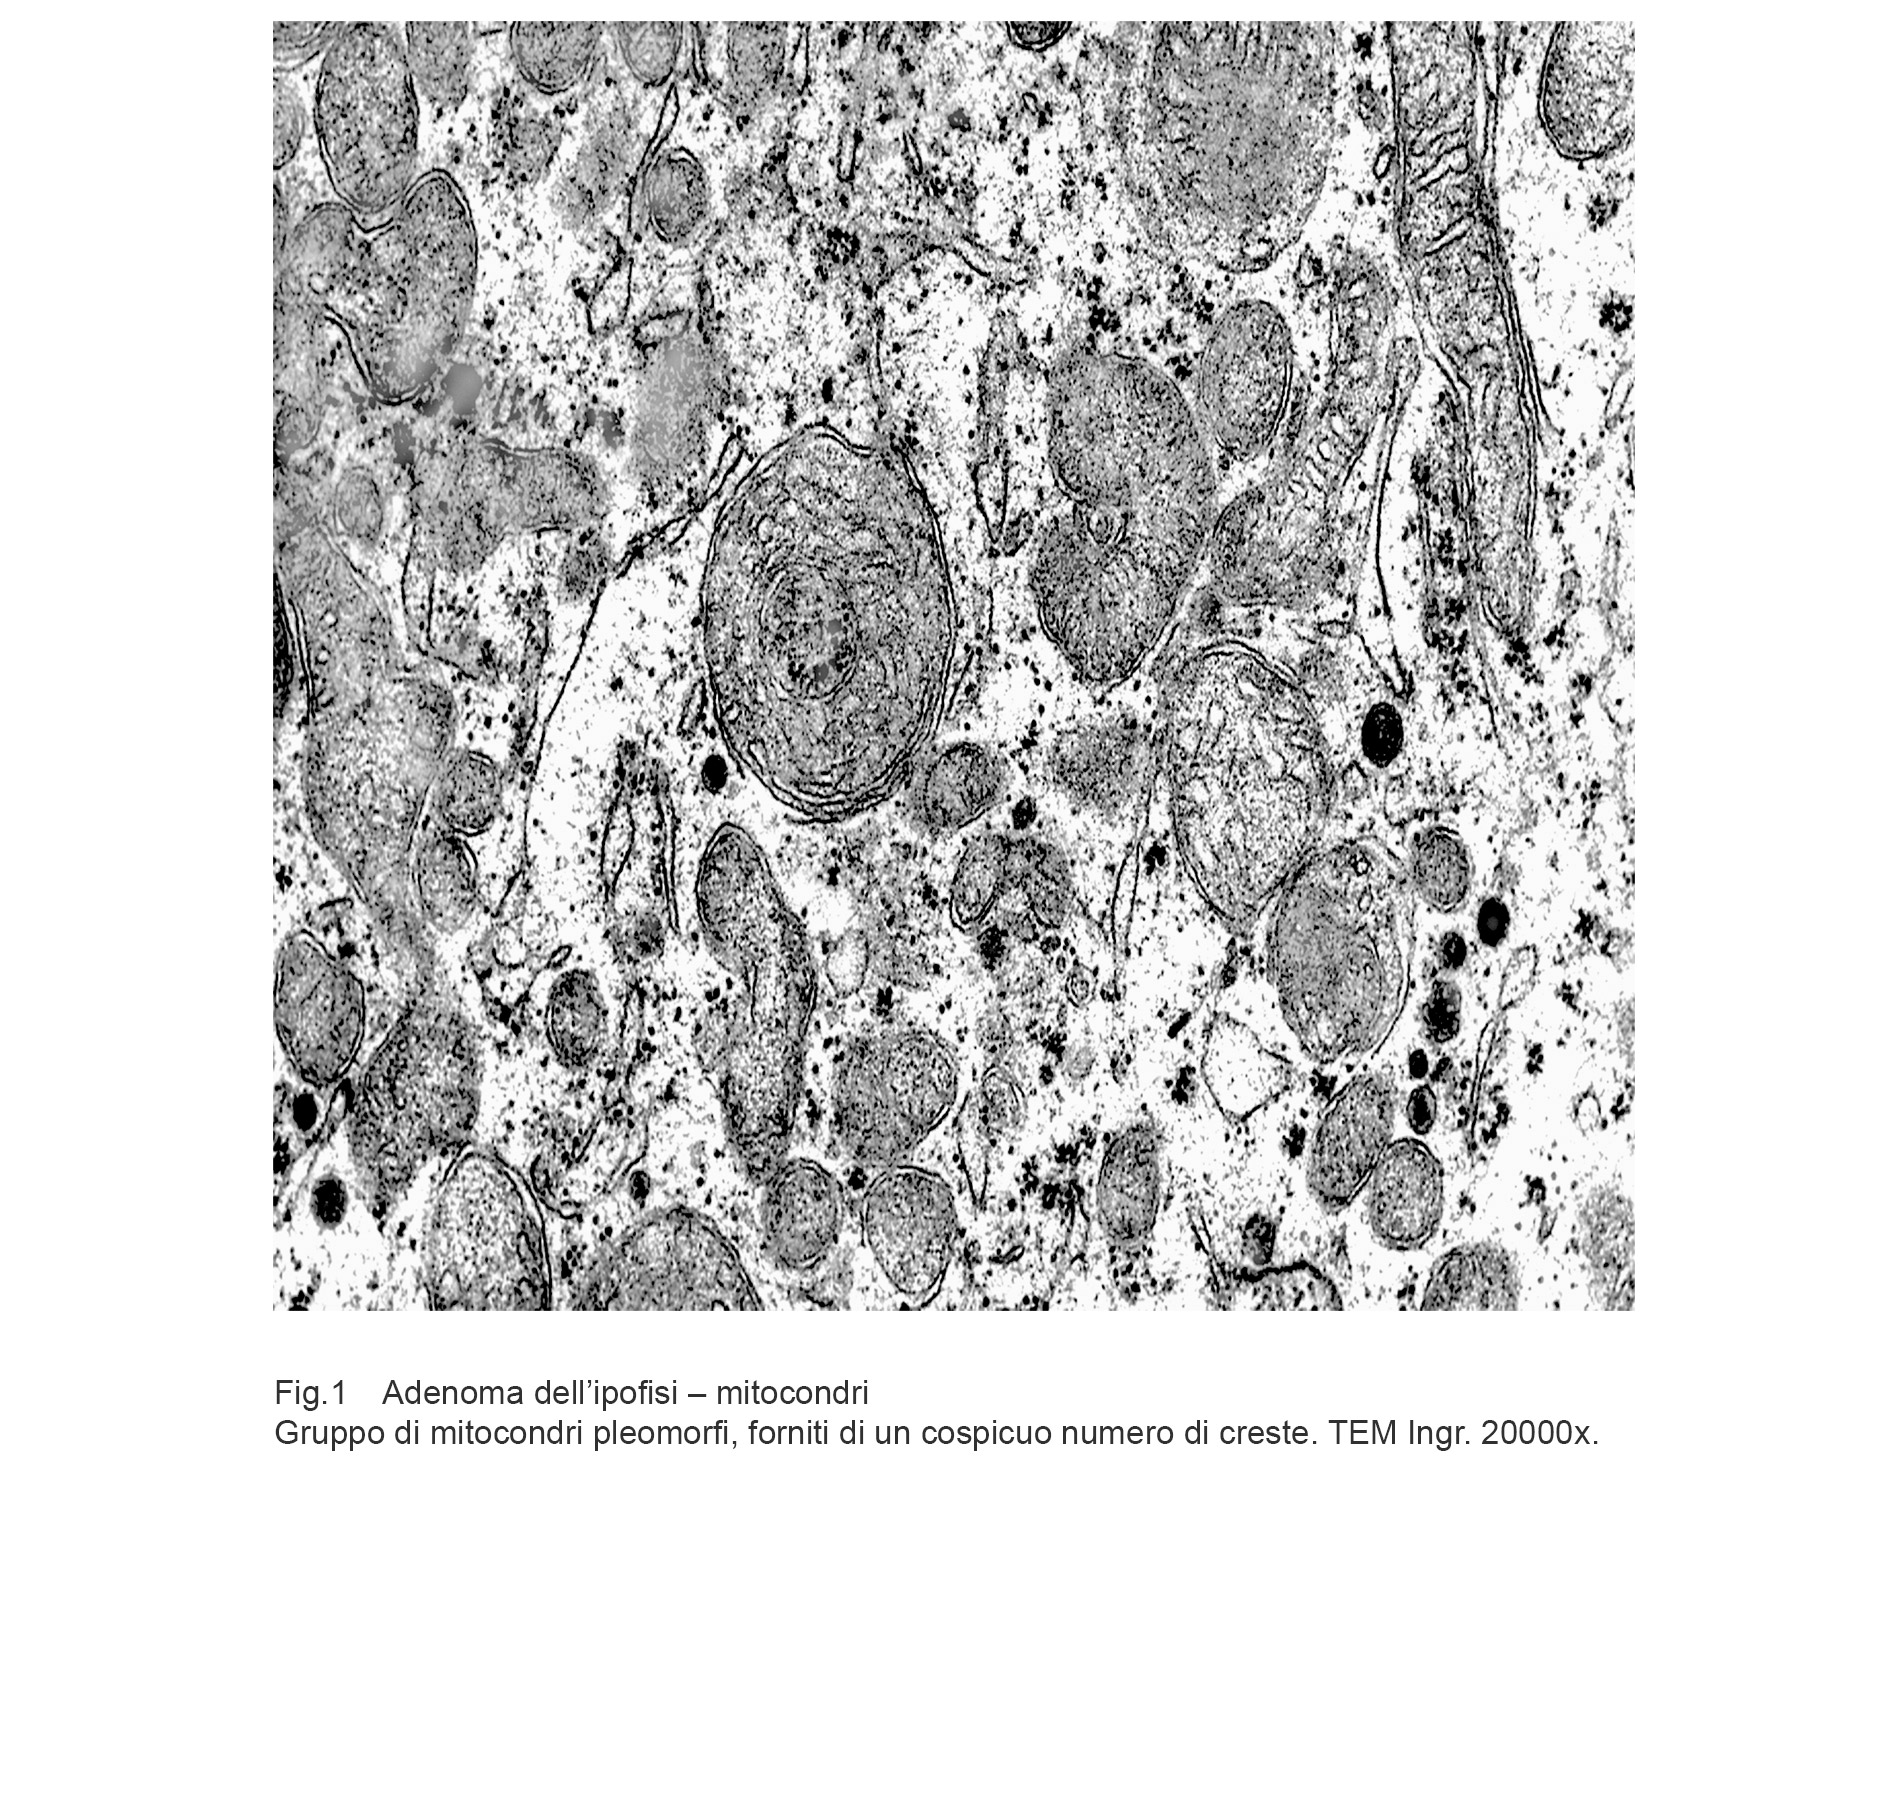

I dati rilevati possono essere sintetizzati nei seguenti punti descrittivi:

Aree citoplasmatiche occupate da mitocondri pleomorfi ben strutturati e forniti di un elevato numero di creste ben disegnate. In queste aree si ritrovano mitocondri in fusione e in fissione.

Fig.1 Fig.2

Cellule in attività secretiva le quali sono fornite di quote cospicue di mitocondri forniti di creste tubulari oppure di mitocondri rigonfi con creste in numero ridotto, spezzettate, disposte spazialmente in modo disordinato.

Fig.3  Fig.4